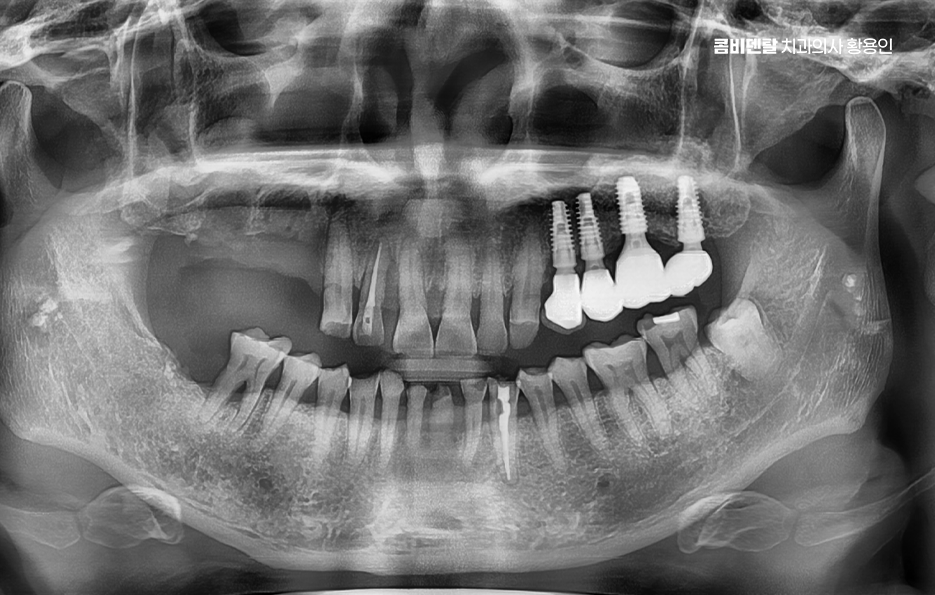

어금니 임플란트 과정은 정밀 진단에서 시작되며 잇몸뼈 안에 인공 치근을 심는 방식이기 때문에 뼈 상태 확인이 필수적으로 파노라마 촬영이나 3차원 CT를 통해 뼈 높이와 폭, 신경 위치를 확인하고 특히 아래 어금니는 하치조신경과 가까워서 정확한 위치 파악이 중요하며 위 어금니는 상악동과의 거리도 고려해야 할 필요가 있어요

임플란트를 심을 잇몸 뼈가 충분하다면 바로 식립이 가능하지만 치아를 빼고 오래 방치한 경우에는 뼈가 흡수되어 부족할 수 있으며 이때는 뼈이식을 먼저 하거나 동시에 진행하고 어금니는 씹는 힘이 강하기 때문에 초기 고정이 단단해야 하며 유지까지 고려할 때 교합의 정교한 맞물림이 중요한 부위라고 할 수 있었어요